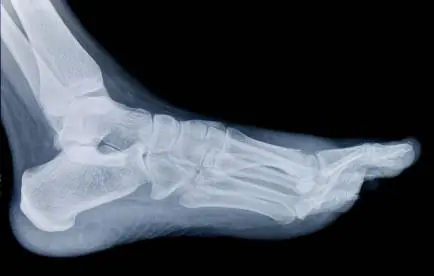

Si te duele la parte baja del talón por un fuerte golpe en esa zona, deberias saber que la mayoria de los casos padeces de esto. Espolón Calcáneo El espolón calcáneo es una protuberancia ósea que se localiza en el hueso del talón llamado calcáneo. Se trata de una calcificación debida a una inflamación crónica en la fascia plantar a la altura del calcáneo. La fascia plantar es un conjunto de tendones y tejido fibroso quese inserta en el talón o calcáneo y que se une con la base de los dedos. En estadios crónicos, y cuando existen factores tales como sobrepeso, calzado inadecuado, hay malas posturas al estar de pie, mal apoyo al andar o se realizan esfuerzos que sobrecargan estos tejidos se produce una inflamación, la cual se termina calcificando y formando el espolón. Síntomas El síntoma primario de la fascitis plantar es el dolor localizado específicamente en el área de carga de peso del talón. Comúnmente es más severo durante los primeros pasos al levantarse de la cama, disminuye en cierta medida con la actividad por la distensión de la fascia, y reaparece de nuevo tras un periodo de descanso. Rara vez hay inflamación visible, enrojecimiento, u otros cambios aparentes en la piel. Es frecuente entre personas que practican deportes, individuos con sobrepeso, personas con arco elevado o pie plano, y a menudo son mujeres con pies largos y estrechos. Tratamiento En principio se puede tratar mediante plantillas que elevan ligeramente el talón y descargan la zona de tensión. También las infiltraciones con corticoides en el punto de dolor son efectivas en muchos casos. En los casos más persistentes se opta por el tratamiento quirúrgico, despegando la fascia de su lugar de origen en el talón. Algunos profesionales también extirpan la calcificación que aparece pegado al calcáneo. Hay que insistir en el hecho de que no es esa calcificación lo que duele, sino la fascia que se origina ahí. Fisioterapia El objetivo inicial de la terapia física es disminuir la inflamación. Luego se fortalecerá los músculos del pie para que presten soporte a la fascia plantar debilitada. Lo más importante es reposar y disminuir la actividad física o el ejercicio. Crioterapia: El masaje con hielo, preferiblemente un par de veces al día o al menos una vez al final del día. Se puede llenar una pequeña botella de plástico con agua y congelarla. Hacer rodar el talón y el arco del pie sobre la botella durante unos 20 minutos proporciona masaje, estiramiento y frío. También podemos acudir al uso de electroterapia para proveer analgesia y ayudar a disminuir la inflamación. Se debe tomar en cuenta que cuando haya cedido la inflamación y el dolor se debe realizar ejercicios de estiramiento y fortalecimiento para así brindar protección al pie. Otras ayudas que podemos tomar en cuenta son: Taloneras y ortesis: Existe una gran variedad de almohadillas para el talón o taloneras, y generalmente son muy útiles. Los soportes blandos, con una almohadilla en el talón son los más eficaces y baratos. Están especialmente indicados en individuos con pie plano o con pronación del antepié. Calzado: Los zapatos con tacón bajo, blando y amplio, y con suela relativamente rígida proporcionan la máxima comodidad y protección. El calzado deportivo es recomendable. Vendajes: La aplicación de tiras de esparadrapo en toda la longitud de la fascia plantar puede ser muy eficaz, especialmente para el dolor agudo y la actividad deportiva. Al principio debe aplicarse a diario. Férulas nocturnas: Las férulas nocturnas mantienen el pie extendido a nivel del tobillo, y son un método eficaz de tratamiento. Yesos: En casos extremadamente agudos o resistentes, la colocación de un yeso de marcha corto durante tres a seis semanas aliviará y ocasionalmente solucionará el problema. Cirugía: Rara vez está indicada. Sin embargo, tras 6 a 12 meses de tratamiento conservador, una liberación quirúrgica parcial de la fascia plantar puede estar indicada. La recuperación tras la intervención generalmente es lenta, a menudo no produce una curación completa, y puede presentar algunas complicaciones. Si te gusto el POST, puntúa.